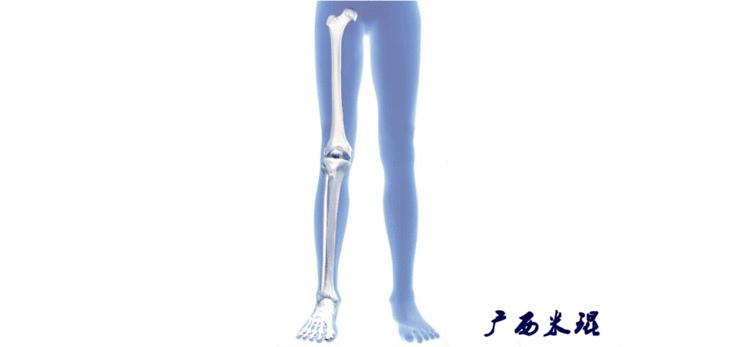

(2)机械轴

机械轴是连接近端和远端关节中心点的直线。

机械轴要分前后位及侧位,站立前后位(也就是冠状面)股骨头中心与踝关节中心的连线通过膝关节中心,这是下肢的机械轴线,也就是下肢力线,常说Mikulicz线。冠状面的力线评估在临床工作中最常用、最基础、最重要。

站立侧位(矢状面)股骨头中心与踝关节中心的连线也通过膝关节中心,这也是下肢的机械轴线,这也是下肢力线。

(3)垂直轴

也就是下肢的负重轴,它是身体的纵轴线,与地面垂直,由于双髋比双踝的距离宽,所以垂直轴与下肢力线(机械轴)存在3°的外翻。

开始接触时可能我们对这些轴有点混乱,通过下面的这张图片就能清楚的了解下肢几个轴之间的关系。